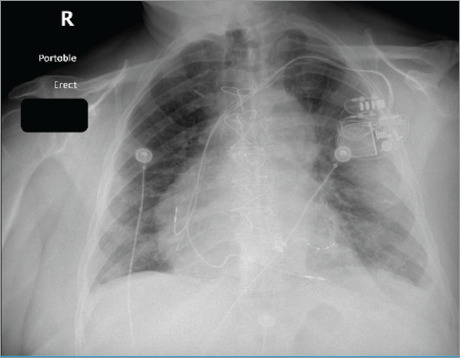

本案例研究探讨了一位80岁男性患者的历程,他有高血压、糖尿病、冠状动脉搭桥术后冠状动脉疾病、心房颤动和心力衰竭的病史。9个月前,因严重的二尖瓣返流,他接受了二尖瓣夹夹术。尽管最初有所改善,但患者再次出现症状,包括休息时呼吸困难和下肢水肿。本病例的结果-发现二尖瓣置换术的需要-为二尖瓣夹断并发症的管理提供了见解,并强调管理需要细致入微的方法。

This case study explores the journey of an 80-year-old male patient with a history of hypertension, diabetes, coronary artery disease after coronary artery bypass grafting, atrial fibrillation, and heart failure. Nine months before he presented to the emergency department, he had undergone mitral valve clipping for severe mitral valve regurgitation. Despite initial improvement, the patient experienced return of symptoms, including dyspnea at rest and lower limb edema. The results of this case-discovery of the need for mitral valve replacement-provides insights into the management of complications from mitral valve clipping and emphasizes that management requires a nuanced, meticulous approach.